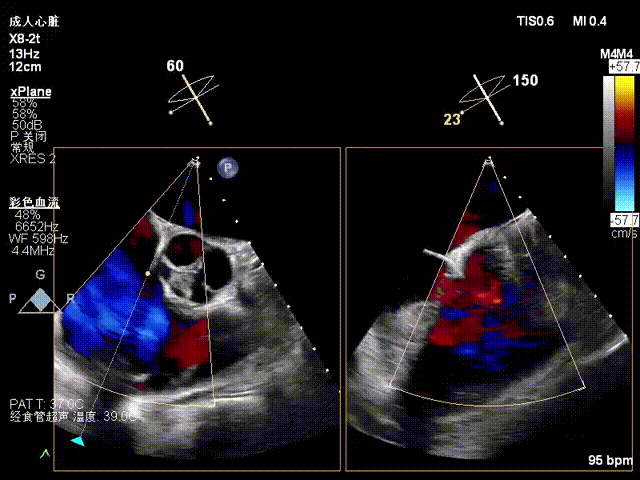

Echocardiographic Findings:Severe tricuspid regurgitation (4+; average vena contracta width, 12 mm). The regurgitation was predominantly anteroseptal and central, with a small posteroseptal component. During systole, the anterior and septal leaflets protruded slightly into the right atrium, with a protrusion height of 2.6 mm. A 6 mm gap was observed at the anteroseptal and central regions. Tricuspid annular dilatation was present (mean annular diameter, 40 mm), with a prominent gap at the anteroseptal region.

Preoperative anteroseptal regurgitation

Preoperative 3D view of regurgitation